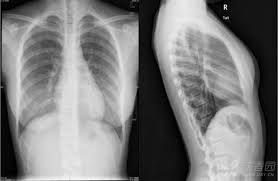

胸片,即胸部x光片,是医学上常用的一种检查手段,主要用于观察肺部、心脏、肋骨等胸部结构的异常情况。胸片曝光是指通过x射线对胸部进行照射,并将影像记录在胶片或数字探测器上的过程。这一过程的目的是为了辅助医生进行疾病诊断,而非满足个人好奇心或娱乐需求。

在获取胸片曝光信息后,患者应保持理性态度,正确解读胸片结果。胸片上的影像信息需要由专业医生进行解读和分析,患者不应自行判断或解读胸片结果,以免因误解或误判而引发不必要的恐慌或焦虑。如果对胸片结果有疑问或担忧,应及时向医生咨询并寻求专业建议。